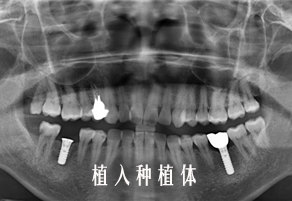

种植牙修复案例(四)

近些年来,人工种植牙固定牙已经被广大医生和患者所熟知,种植牙就和自己的牙齿一样,没有多余的钢丝,基托,也不用磨损旁边的好牙齿,是现下比较理想的修复方法。那么到底种植牙是怎么生长出来的呢?宁德中富口腔来告诉大家,人工种植牙的那些奥秘。